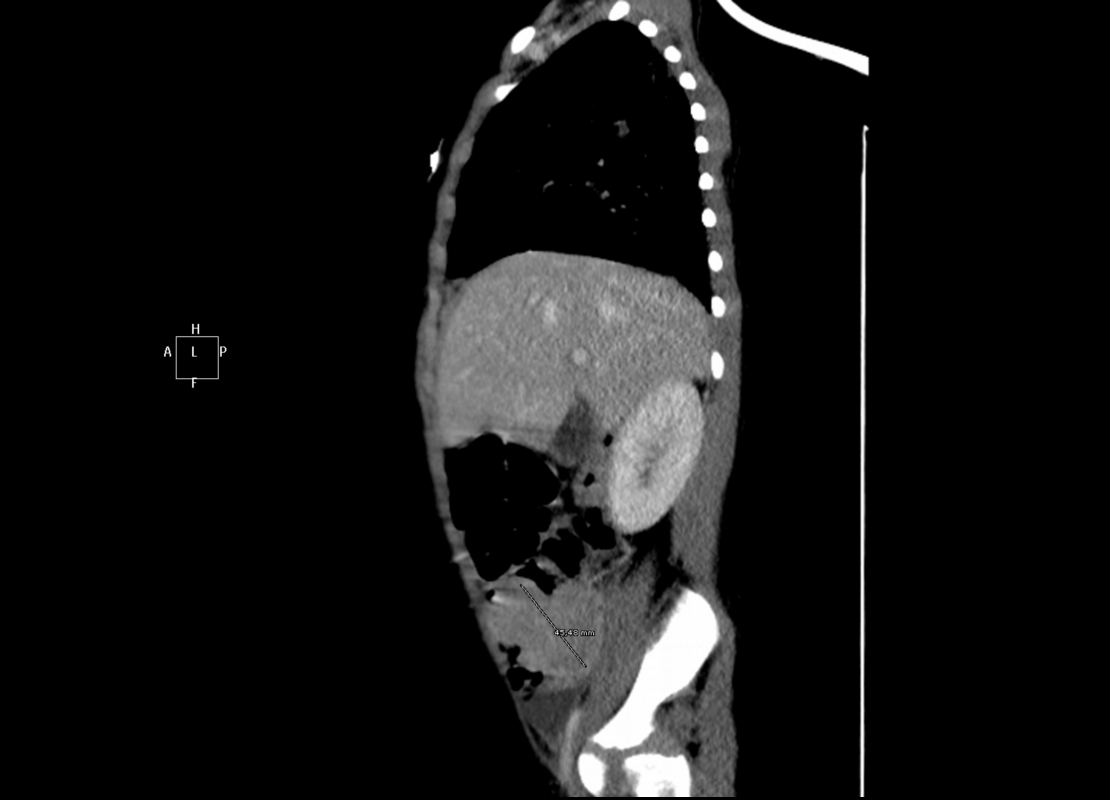

Ante la nueva sospecha diagnóstica se realiza una tomografía computarizada (TC) cráneo-cérvico-toraco-abdominal, en la que se observa una masa en la fosa iliaca derecha y una lesión ósea agresiva maxilomandibular derecha, junto con una adenopatía submandibular ipsilateral.